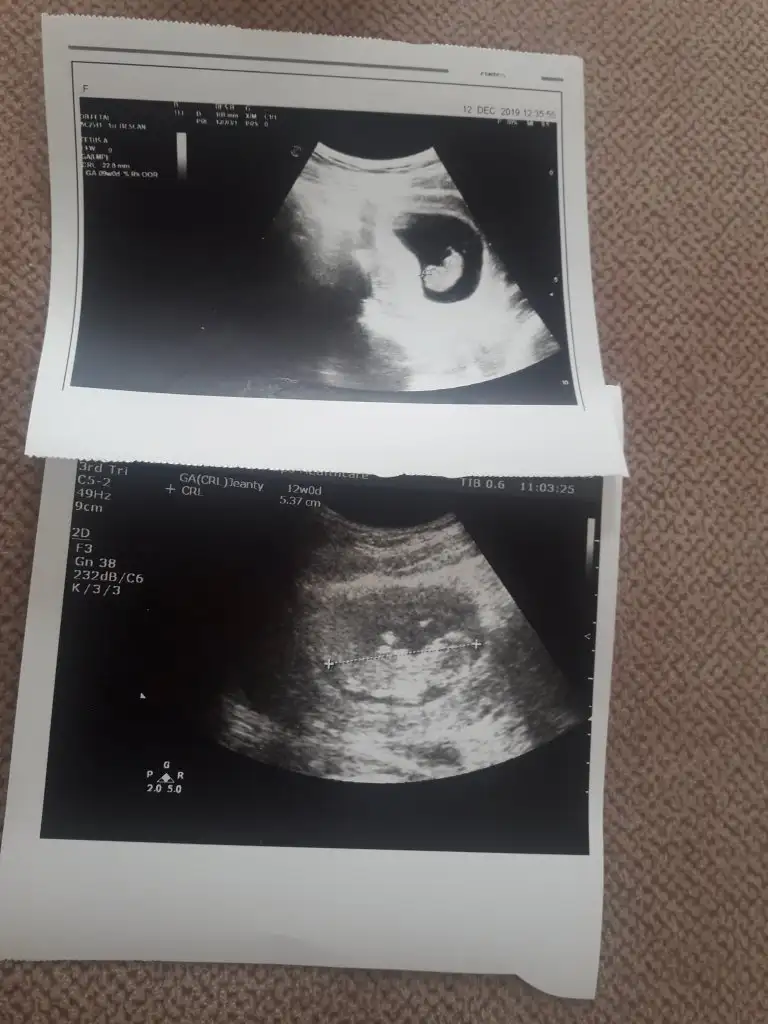

Ilk 9cu hafta ikincisi 12ci hafta

Benim iki oğlum var ikisinin de kesesi şekilsizdi ve fasulye gibi değillerdi düz çubuk gibilerdi. Ondan önceki iki defa kürtaj oldum onlar fasulye gibiydi ve keseleri yuvarlaktı onlar kızdı. Bir tane de evde düşürdüm WC de hemen pamuğa aldım çubuk gibiydi yine erkekti. Sanırım kese artı ilk oluşum şekli belli ediyor